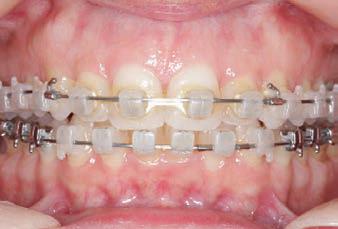

Carriere Motion 3D Appliance

Fastrack your orthodontic treatments. Save 6 months or more.

The SAGITTAL FIRST™ Philosophy is a time-tested approach that standardises, simplifies, and shortens Class II and Class III treatment times. It employs the Carriere Motion 3D Appliance to treat the AP dimension at the beginning of treatment before placing brackets or aligners. By resolving the most difficult part of treatment first, you can achieve a Class I platform in 3 to 6 months, shortening total treatment time by a minimum of 6 months1. You know how excited patients and parents become when you mention shorter treatment times.

CLASS II DIV.1 - Marra

PROVIDED BY: DR. LUIS CARRIÈRE

INITIAL - 4/4/18

PROGRESS 1 - 26/9/18 - Class I platform accomplished in 5.75 months with Motion 3D COLOR Appliance

PROGRESS 2 - 26/9/18 - Placement of the SLX 3D Clear Brackets

[CONTINUED ON NEXT PAGE]

with M-ONE .015 Cu Nitanium 27°

PROVIDED BY: DR. LUIS

PROGRESS 3 - 30/10/18 - With M-TWO .020 x .020 Cu Nitanium 35° archwire

PROGRESS 4 - 27/11/18 - 3 links power chain: 5, 4, bypass 3 to crimp hooks

PROGRESS 5 - 13/3/19 - With M-TWO .020 x .020 Cu Nitanium 35° archwire

PROGRESS 6 - 1/8/19 - With M-THREE.019 x .025 Beta Titanium wire

52 HENRY SCHEIN ORTHODONTICS

FINAL - 10/10/19 - Appliances removed AFTER

PROGRESS 7 - 10/10/19 - Final day in SLX 3D Clear Brackets BEFORE